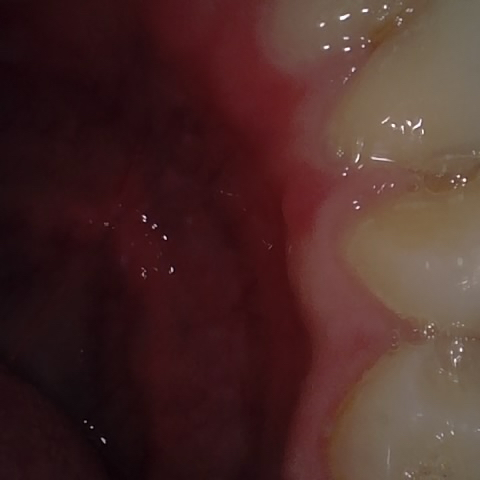

Annotated as "Good"